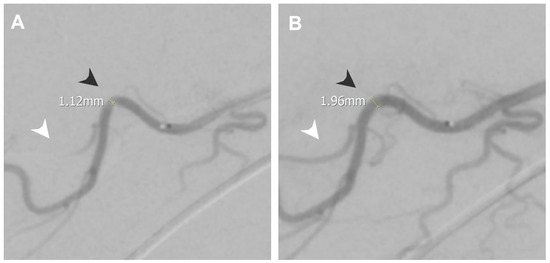

3.6. Secondary Stiff Shoulder

| Secondary stiff shoulder | Thoracoacromial artery | 1.12 | 1.96 |